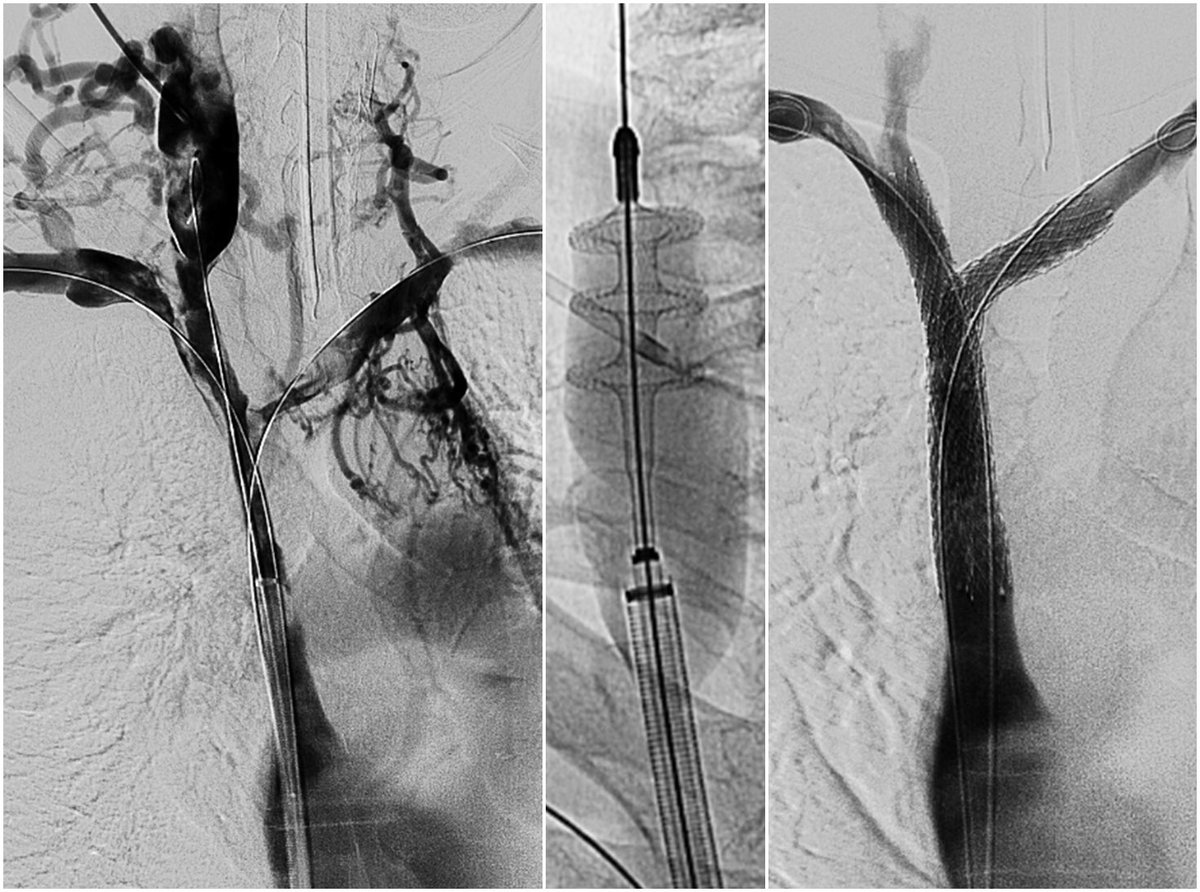

Acute and chronic venous occlusive disease of head, neck, and chest may be repaired and native veins may be restored using single-session thrombectomy and stent reconstruction. Interventional Radiologists may help. #IRAD @davidsshin @FredBertinoMD @UofWa_IR @SIRspecialists

65 yo w/pancreatic ca and progressive abdominal pain found to have a severe stenosis at the portal confluence. Stenosis stented via transjugular access w/ significant reduction in pain post-procedure. #IRad #PatientCentered @SIRRFS @SIR_ECS @JVIRmedia @MFickesMD @ncdoro